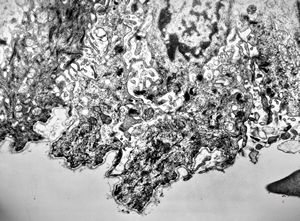

oral saprophytic bacterium